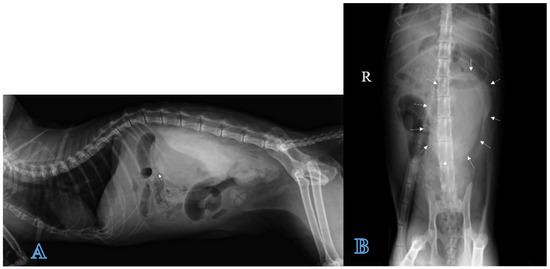

A direct radiographic study of the abdomen with orthogonal projections was performed, using a radiographic system (Morpheus, Gieffe Elettromedicali, Misterbianco (Catania, Italy) and a digital radiography system (Fujifilm Medical Systems, Milan, Italy). This examination showed a loss of soft tissue contrast in the lumbar region, and radiopaque stones in the urinary bladder (Figure 1).

Figure 1.

Lateral radiograph of the abdomen: loss of contrast in the lumbar region (arrows) and a presence of uroliths in urinary bladder.

Positive contrast radiographs in the lateral and ventrodorsal projections immediately after the injection of the contrast agent allowed for defining the extent of the lesion, outlining the fluid collection as a large well-marginated homogeneous radiopaque area in the left retroperitoneal space and differentiating it from ascite (Figure 5A,B).

Figure 5.

Positive contrast X-ray exam of the abdomen: (A) Left lateral and (B) ventrodorsal projections. Contrast medium that borders the fluid collection is shown in arrows.